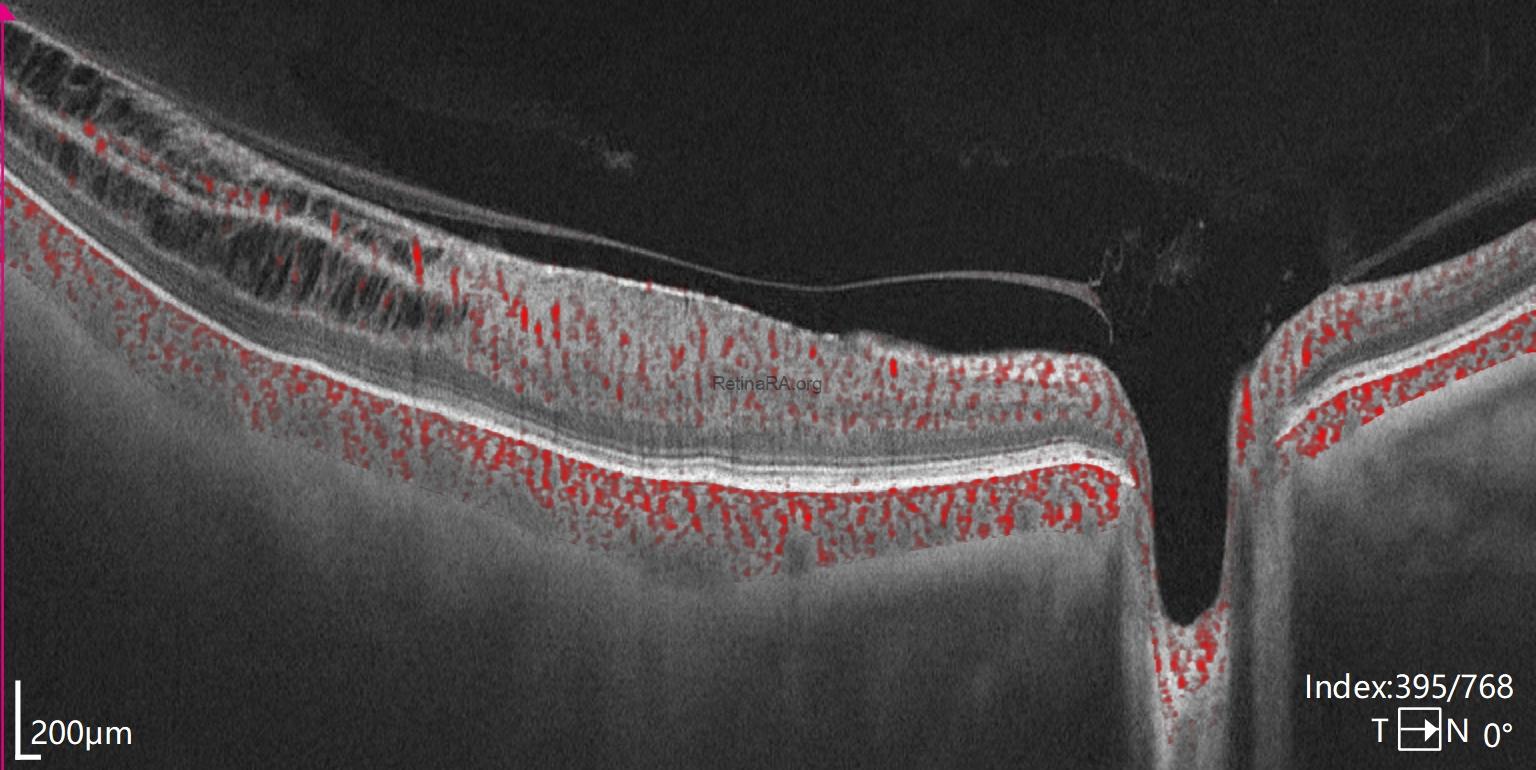

B-scan OCT shows us the loss of foveal depression due to ERM. In the upper scan, the posterior hyaloid appears attached to the optic disc. The lower OCT scan shows that, the posterior hyaloid remains attached to the retina in the temporal macular region where the retinoschisis appearance and damaged retina were present.

In the upper OCT, marked thinning of the temporal retina was visible. Disruptions were observed especially within the retinal nerve fiber layer and the ganglion cell layer.